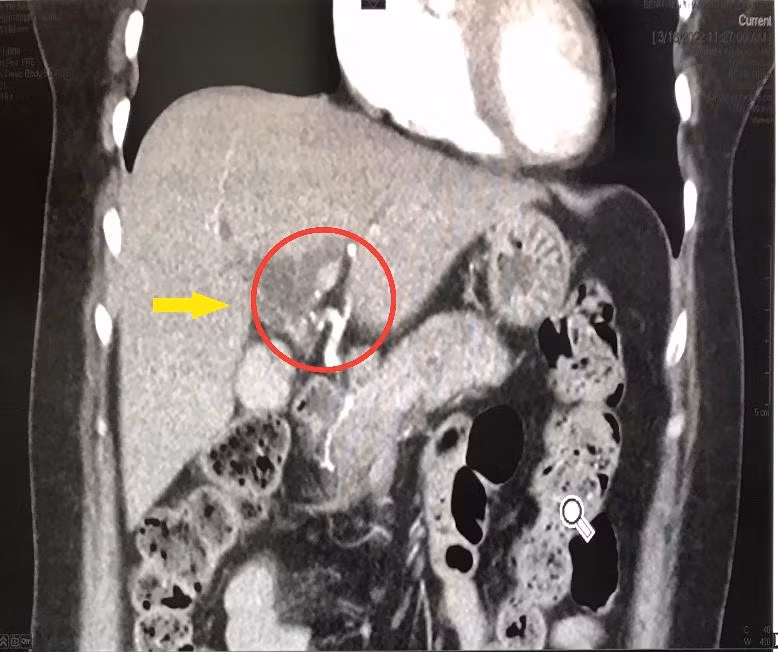

Qua thăm khám sàng lọc kỹ lưỡng và thực hiện các cận lâm sàng cần thiết, các bác sĩ chuyên khoa chẩn đoán bệnh nhân bị tắc mật ngoài gan do khối u đường mật rốn gan (U Klaskin) ác tính - một loại ung thư đường mật vùng rốn gan hiếm gặp, không thể phẫu thuật triệt căn.

Hình chụp CT cắt lớp vi tính 3D phát hiện khối U đường mật rốn gan ác tính. Ảnh: BV.

Theo bác sĩ Chuyên khoa 1 Dương Hải Minh, Trưởng Khoa ngoại Lồng ngực - Mạch máu và Tổng quát, đây là một trường hợp ca bệnh nặng, hiếm gặp, bệnh chiếm tỉ lệ khoảng 2% ung thư đường tiêu hóa. Nếu không phát hiện sớm, can thiệp kịp thời, bệnh sẽ tiến triển nặng dẫn đến tắc mật hoàn toàn, suy gan cấp, nhiễm trùng, nhiễm độc nặng, gây nguy hiểm đến tính mạng người bệnh, dẫn đến tử vong.